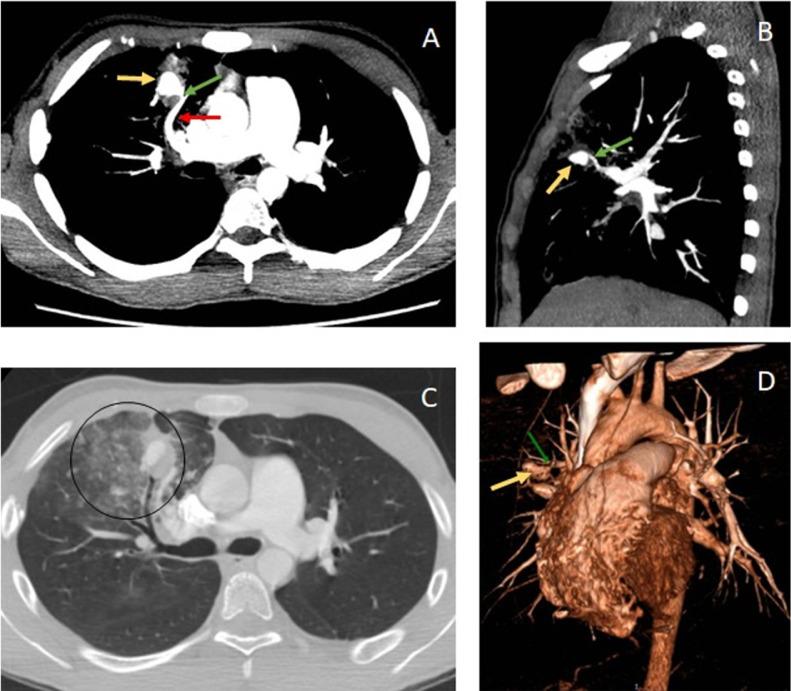

Pseudoaneurysms of a pulmonary artery branch are a rare complication in cases of penetrating chest trauma. Other more frequent causes are secondary to infections or iatrogenesis. We present the case of a 16-year-old male patient who returns weeks after having sustained a stab wound to the chest, complaining of hemoptysis and chest pain. Imaging studies help detect and characterize a partially thrombosed pseudoaneurysm arising from the artery that supplies the anterior segment of the right upper lobe, with an associated post-traumatic pulmonary arteriovenous fistula. The patient was successfully treated with endovascular arterial embolization. Identifying this entity opportunely has an impact on the survival of this patient, avoiding risk secondary to massive bleeding by making an adequate treatment.

肺动脉分支假性动脉瘤是穿透性胸部创伤病例中一种罕见的并发症。其他更常见的病因继发于感染或医源性因素。我们报告一例16岁男性患者,该患者在胸部被刺伤数周后复诊,主诉咯血和胸痛。影像学检查有助于检测和确定一个由供应右上叶前段的动脉形成的部分血栓形成的假性动脉瘤,并伴有创伤后肺动静脉瘘。该患者通过血管内动脉栓塞术成功治愈。及时识别这一病症对该患者的生存具有重要意义,通过进行适当治疗可避免大出血带来的风险。